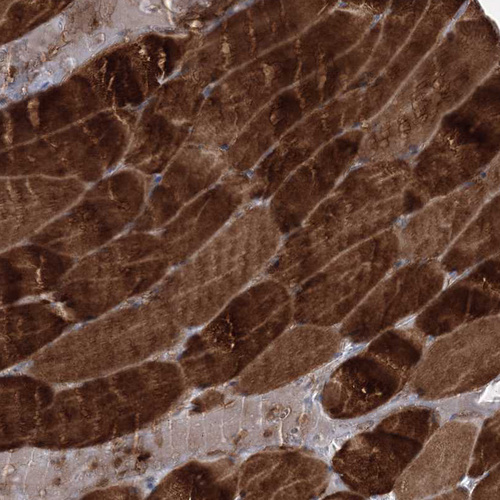

Immunohistochemical staining of human testis shows moderate cytoplasmic positivity in Leydig cells.